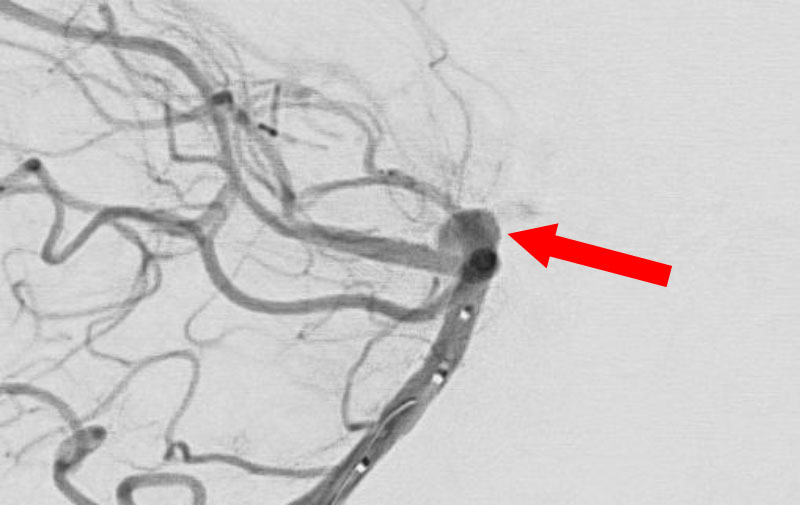

No.1630 手術前

No.1630 手術中

No.1630 手術後